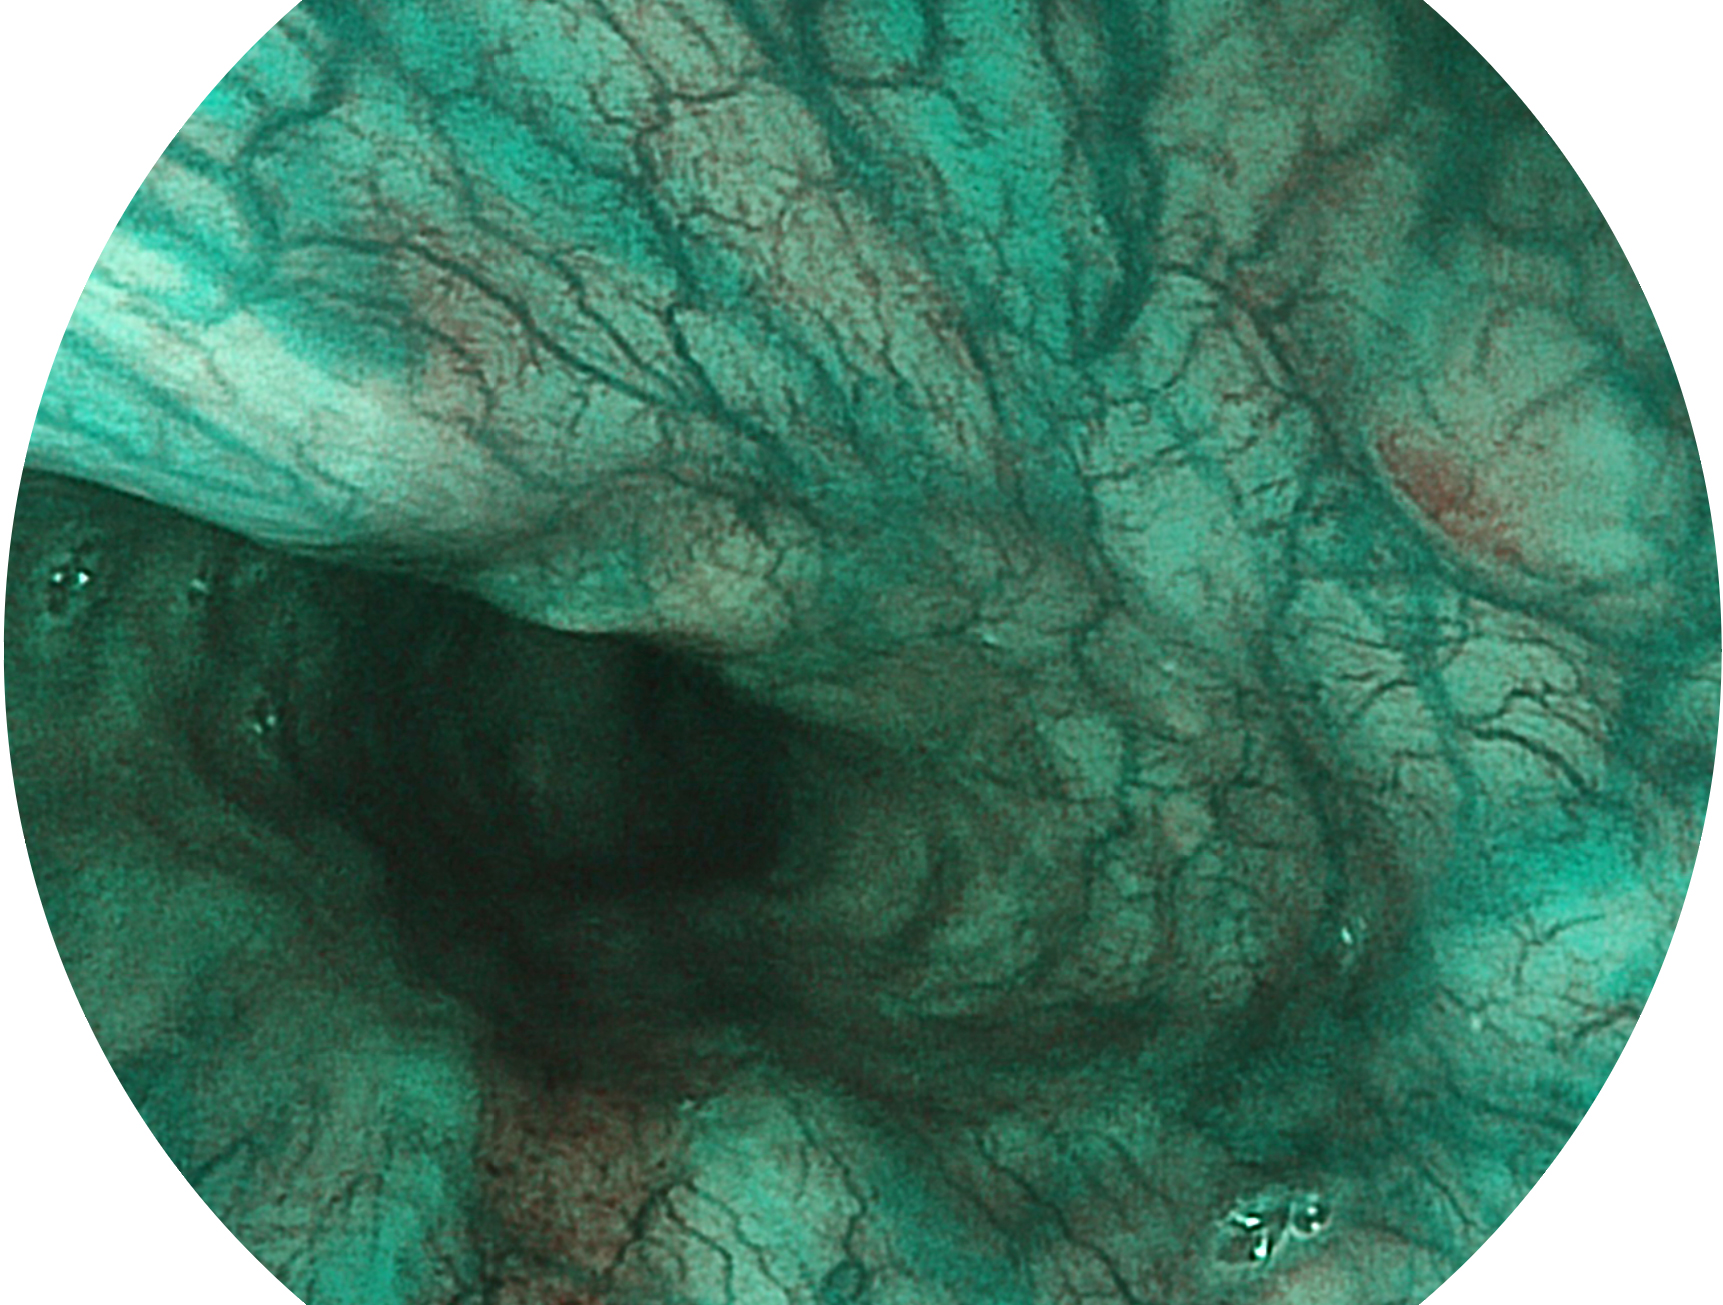

玖鼎集团新开发的内镜染色技术,主要是基于多波长LED 光源的开发,VLS-55Q 四波长LED 光源是由四个不同颜色的LED光按照相应照明模式所规定的特定发光比例进行合束后形成,合束后形成的照明光的光谱由红光、绿光、蓝光及蓝紫光这四个不同的波段范围构成。具有更高光谱自由度,通过光谱比例的控制,实现了聚谱成像技术,英文全称为“Spectral Focused Imaging, SFI”,缩写为“SFI”和光电复合染色成像技术,英文全称为“Versatile Intelligent Staining Technology, VIST”,缩写为“VIST”。